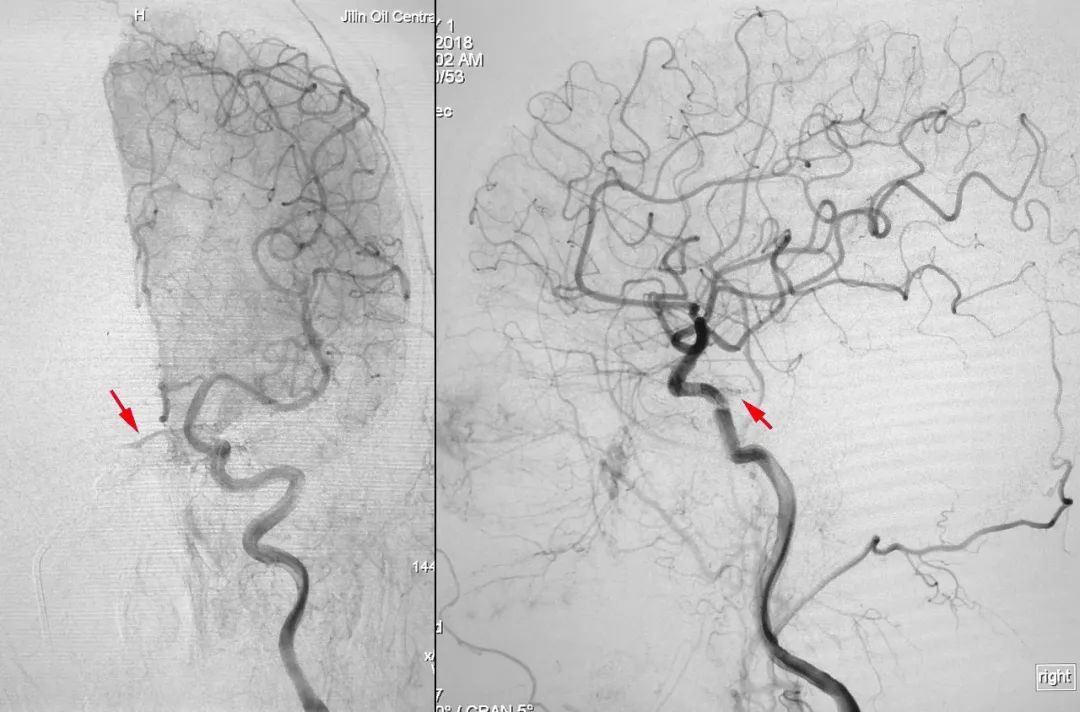

右侧颈内动脉正、侧位造影:

右侧颈内动脉造影三维重建示右侧岩下窦在汇入颈内静脉处有狭窄:

左侧颈总动脉正、侧位造影: